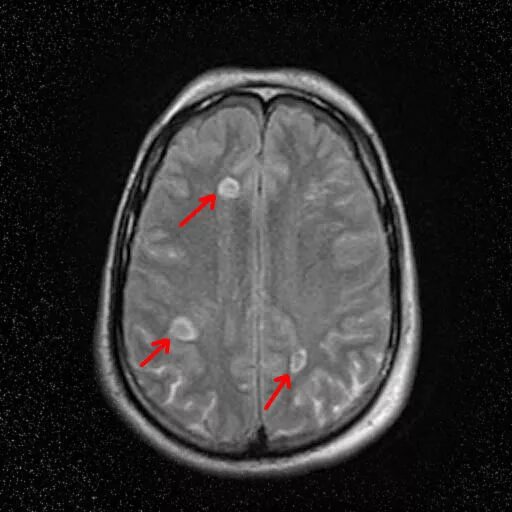

Диффузное поражение головного